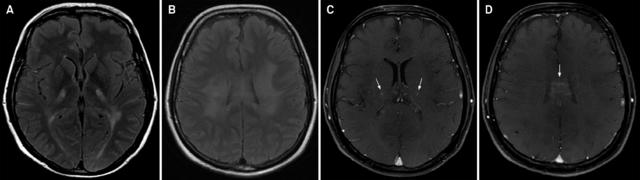

案例 1:36 岁男性,诊断为肾上腺脊髓神经病。

图 1 A~B:FLAIR 可见双侧深部白质,胼胝体体部和内囊高信号;C~D:T1 增强可见内囊和胼胝体体部病灶强化

案例 2:54 岁男性,诊断为肾上腺脑白质营养不良。

图 2 A~B:T2WI / FLAIR 提示双侧额叶皮质下、脑室旁和顶枕叶白质受累,同时可见内囊高信号。C:T1 增强提示额叶病灶周围轻度强化

案例 3:28 岁男性,诊断为肾上腺脑白质营养不良。数月前曾有右顶叶区外伤史。

图 3 A:FLAIR 证实右侧顶叶皮质下白质病灶;B:T1 增强可见病灶边缘非连续性强化;C:T2WI 可见异常信号延伸至内囊;D:DWI 可见病灶边缘高信号